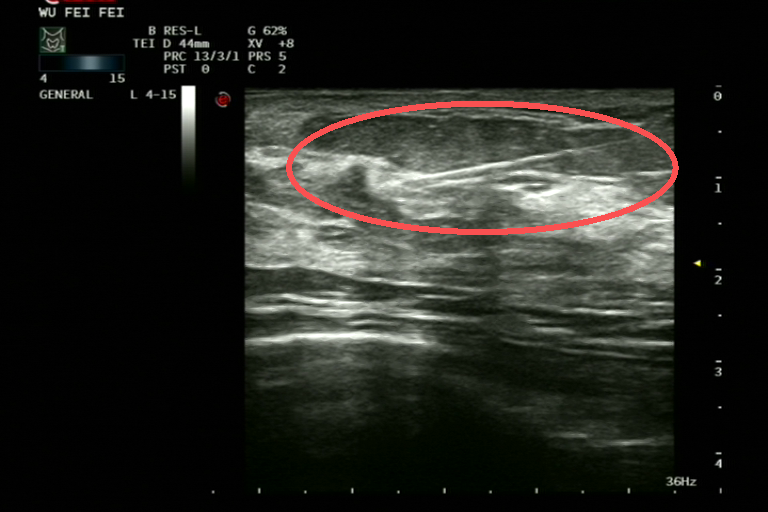

▲ 手术在超声引导下进行

手术在超声引导下进行,在乳腺原发病灶中心精准释放标记夹,整个操作微创、安全患者耐受性好

▲ 在乳腺原发病灶中心精准释放标记夹

郝静介绍,乳腺组织定位标记夹是一种微小、安全、可永久留置体内的医用标记物在影像学上清晰可见,无论是超声、钼靶还是磁共振,都能准确定位,也为多学科联合诊疗提供了依据。